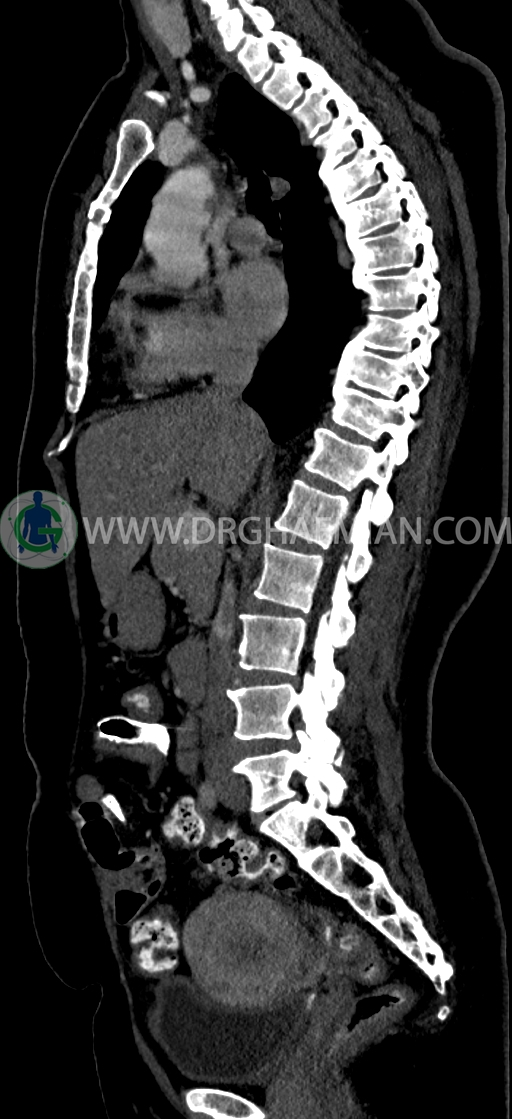

–Bridging osteophyte در مهره هاي توراسيک مطرح کننده DISH همراه با کيفوز مشهود است.